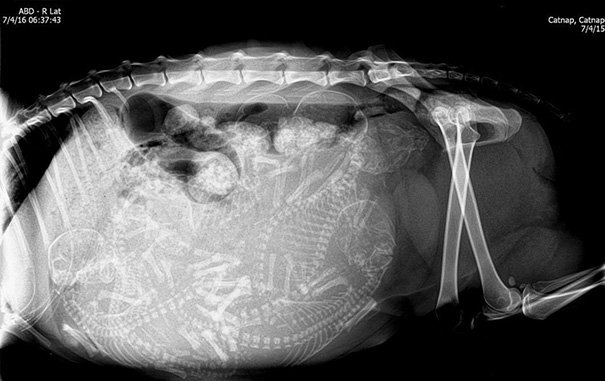

кошка